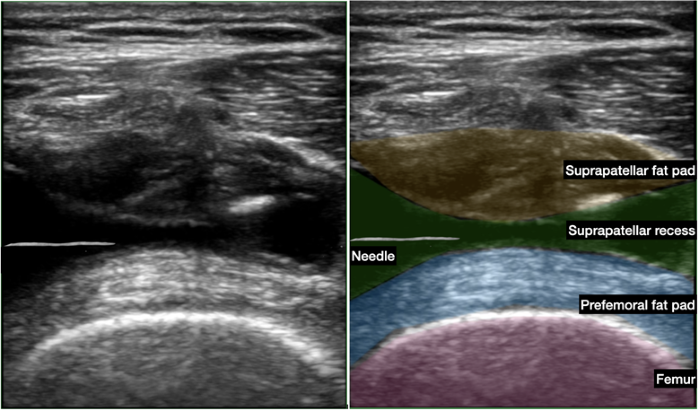

- Needle Insertion: Choose an appropriate needle length (typically 1.5 to 2 inches) and gauge (eg, 21- or 22-gauge) for the injection. Insert the needle parallel to the probe in a lateral to medial direction at the depth of the suprapatellar recess identified during the prescan (Figure B). Use ultrasound guidance while visualizing the needle tip to confirm the needle's entry into the suprapatellar recess.

- Medication Administration: Administer the prescribed medication (eg, Triamcinolone is standard) mixed with 4-5 ml of local anesthetic. Ensure slow and steady administration while monitoring under ultrasound for accurate placement and to avoid vascular uptake (Figure C).

Figure C. Ultrasound images of injection depicting injection into the suprapatellar recess. Needle is in between the suprapatellar fat pad (yellow) and prefemoral fat pad (blue)